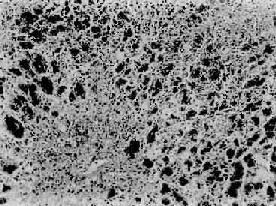

(2)慢性活动性肝炎(chuonic active hepatitis,CAH):此型肝炎病变较重,肝功能持续异常。镜下,肝细胞变性坏死更为广泛而严重。肝细胞坏死呈灶状或条带状,并具有以下二种特征。①小叶周边的肝细胞界板受到破坏,界板肝细胞呈灶状坏死、崩解,伴有炎性细胞浸润,称为碎片状坏死(piecemeal necrosis)(图10-37);②小叶中央静脉与汇管区之间或两个中央静脉之间出现肝细胞坏死带,称桥接坏死(bridging necrosis)。坏死区可出现肝细胞不规则再生。小叶周边部坏死区纤维组织增生呈星芒状向小叶内伸展,并与小叶内肝细胞坏死处网状纤维支架塌陷而胶原化的纤维条索相连接,形成纤维间隔而分割小叶结构。肉眼观,在肿大的肝表面,上述纤维化明显区呈不平滑颗粒状,质地较硬。此型常见于乙、丙型肝炎,除肝外,患者还有脾肿大等全身改变,如不及时治愈大都转入肝硬变。

慢性活动性肝炎

图10-37 慢性活动性肝炎

肝细胞明显气球样变和嗜酸性变,小叶界板破坏呈现碎片状坏死,门管区见炎性细胞浸润